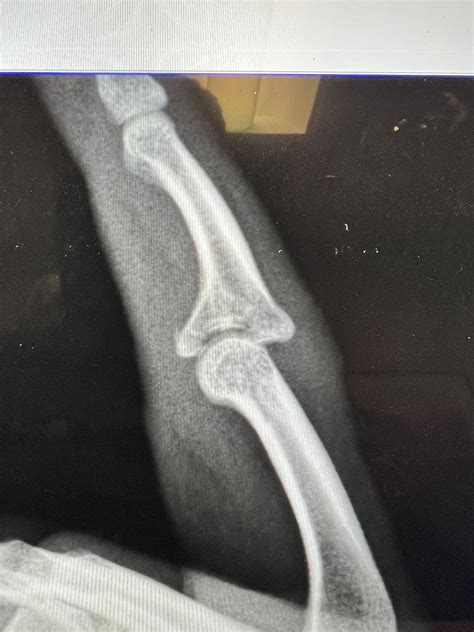

One of the most common injuries in rock climbing is a finger jam or break. This can happen due to improper technique, overuse, or sudden impacts. Here are some tips to avoid these injuries: